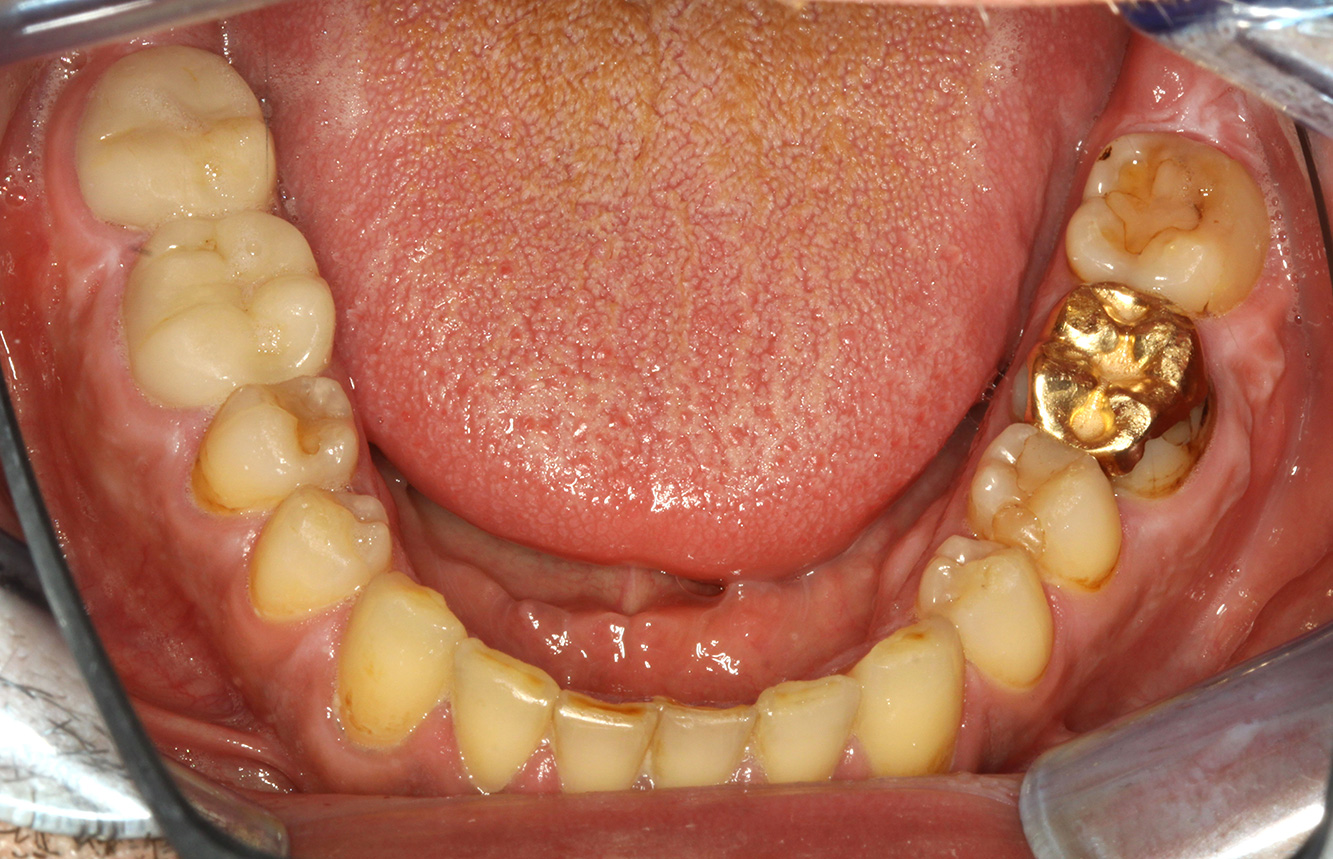

El paciente tiene 39 años con valvuloplastia frente a una insuficiencia valvular y endocarditis. Toma regularmente ASS 100 (ácido acetil salicílico) como anticoagulante. En el ámbito del estilo de vida, la alimentación se identifica como promotora de caries, ya que suele consumir alimentos azucarados y seis o siete comidas al día. La salud oral del paciente muestra un riesgo medio de caries con lesiones activas. El riesgo de periodontitis es bajo, presenta gingivitis. Se hacen las siguientes recomendaciones para el tratamiento profiláctico.

Para la sesión de profilaxis no hay recomendaciones específicas de instrumental. Mediante el uso dirigido de un aeropulidor y del pulido rotativo, puede eliminarse suavemente la placa y la decoloración en los bordes de la restauración y reducirse los nichos de recolonización para bacterias carcinógenas (19).

Para prevenir aún más las caries, se recomienda la fluoridación, especialmente para prevenir la nueva formación en el área de los márgenes de restauración y para sellar las superficies radiculares. Ambas medidas pueden reducir la sensibilidad a la temperatura de los dientes.